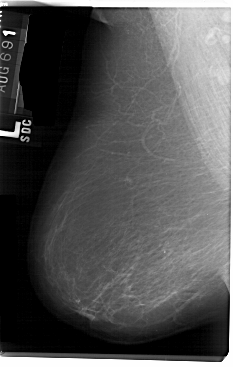

A_1111_1.LEFT_MLO

LEFT_MLO LINES 5491 PIXELS_PER_LINE 3481 BITS_PER_PIXEL 12 RESOLUTION 43.5 NON_OVERLAY